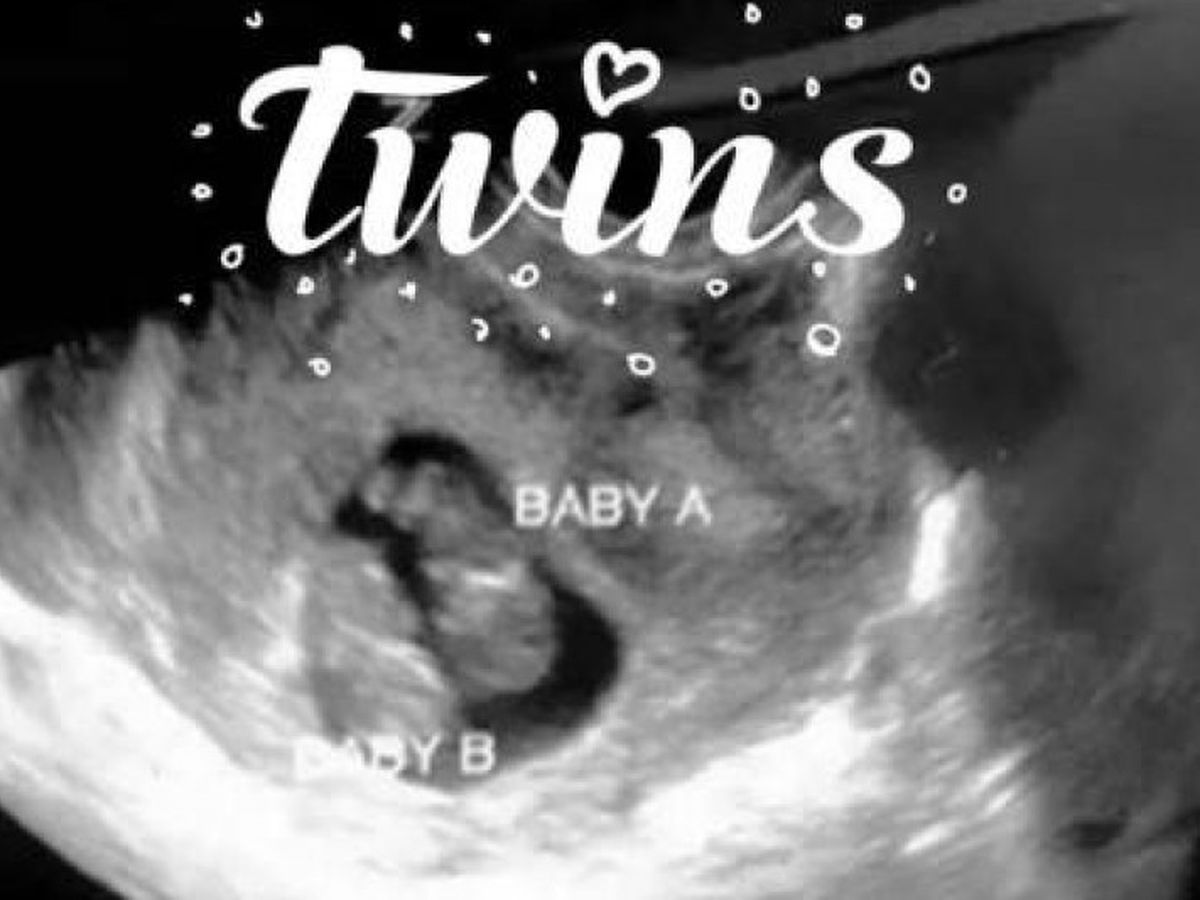

Twin boys, Tosin and Felix, are several weeks away from making it to a full term delivery date, but the likelihood of that happening are low. The boys are Monochrionic Diamniotic Twins, mono/di, meaning they are sharing the same placenta, which is their blood supply, leaving them more susceptible to complications for the rest of the pregnancy and into their lives. Felix has already been affected by mono/di, resulting in improper growth, from a diagnosis of Intrauterine Growth Restriction, IUGR. He also has a cleft lip with possible palate involvement that will pose a series of problems for him with feeding initially and will need to be corrected when the time is appropriate.

On behalf of the parents of these two wonderful boys, Dianna and Joey, I’m asking for prayers and any financial support that you can offer – no amount is too small and the proceeds will bless them abundantly. Dianna has been restricted from working, and will remain with her twins (and their big brother, Junior) to care for her newborns special needs. She is currently 33 weeks along and set for induction at 37 weeks unless they make a surprise appearance before then. The top weight possible for each baby is 4 pounds, but is unlikely being that Tosin currently weighs 2 lbs and 9 oz and his brother Felix weighs 2 lbs and 3 oz. They will spend their NICU time at Detroit Children’s Hospital, which is over an hour commute each way, until they are strong enough to join the rest of their family at home. Please keep this amazing family in your thoughts and prayers as they embark on this wonderful journey with their new twins!